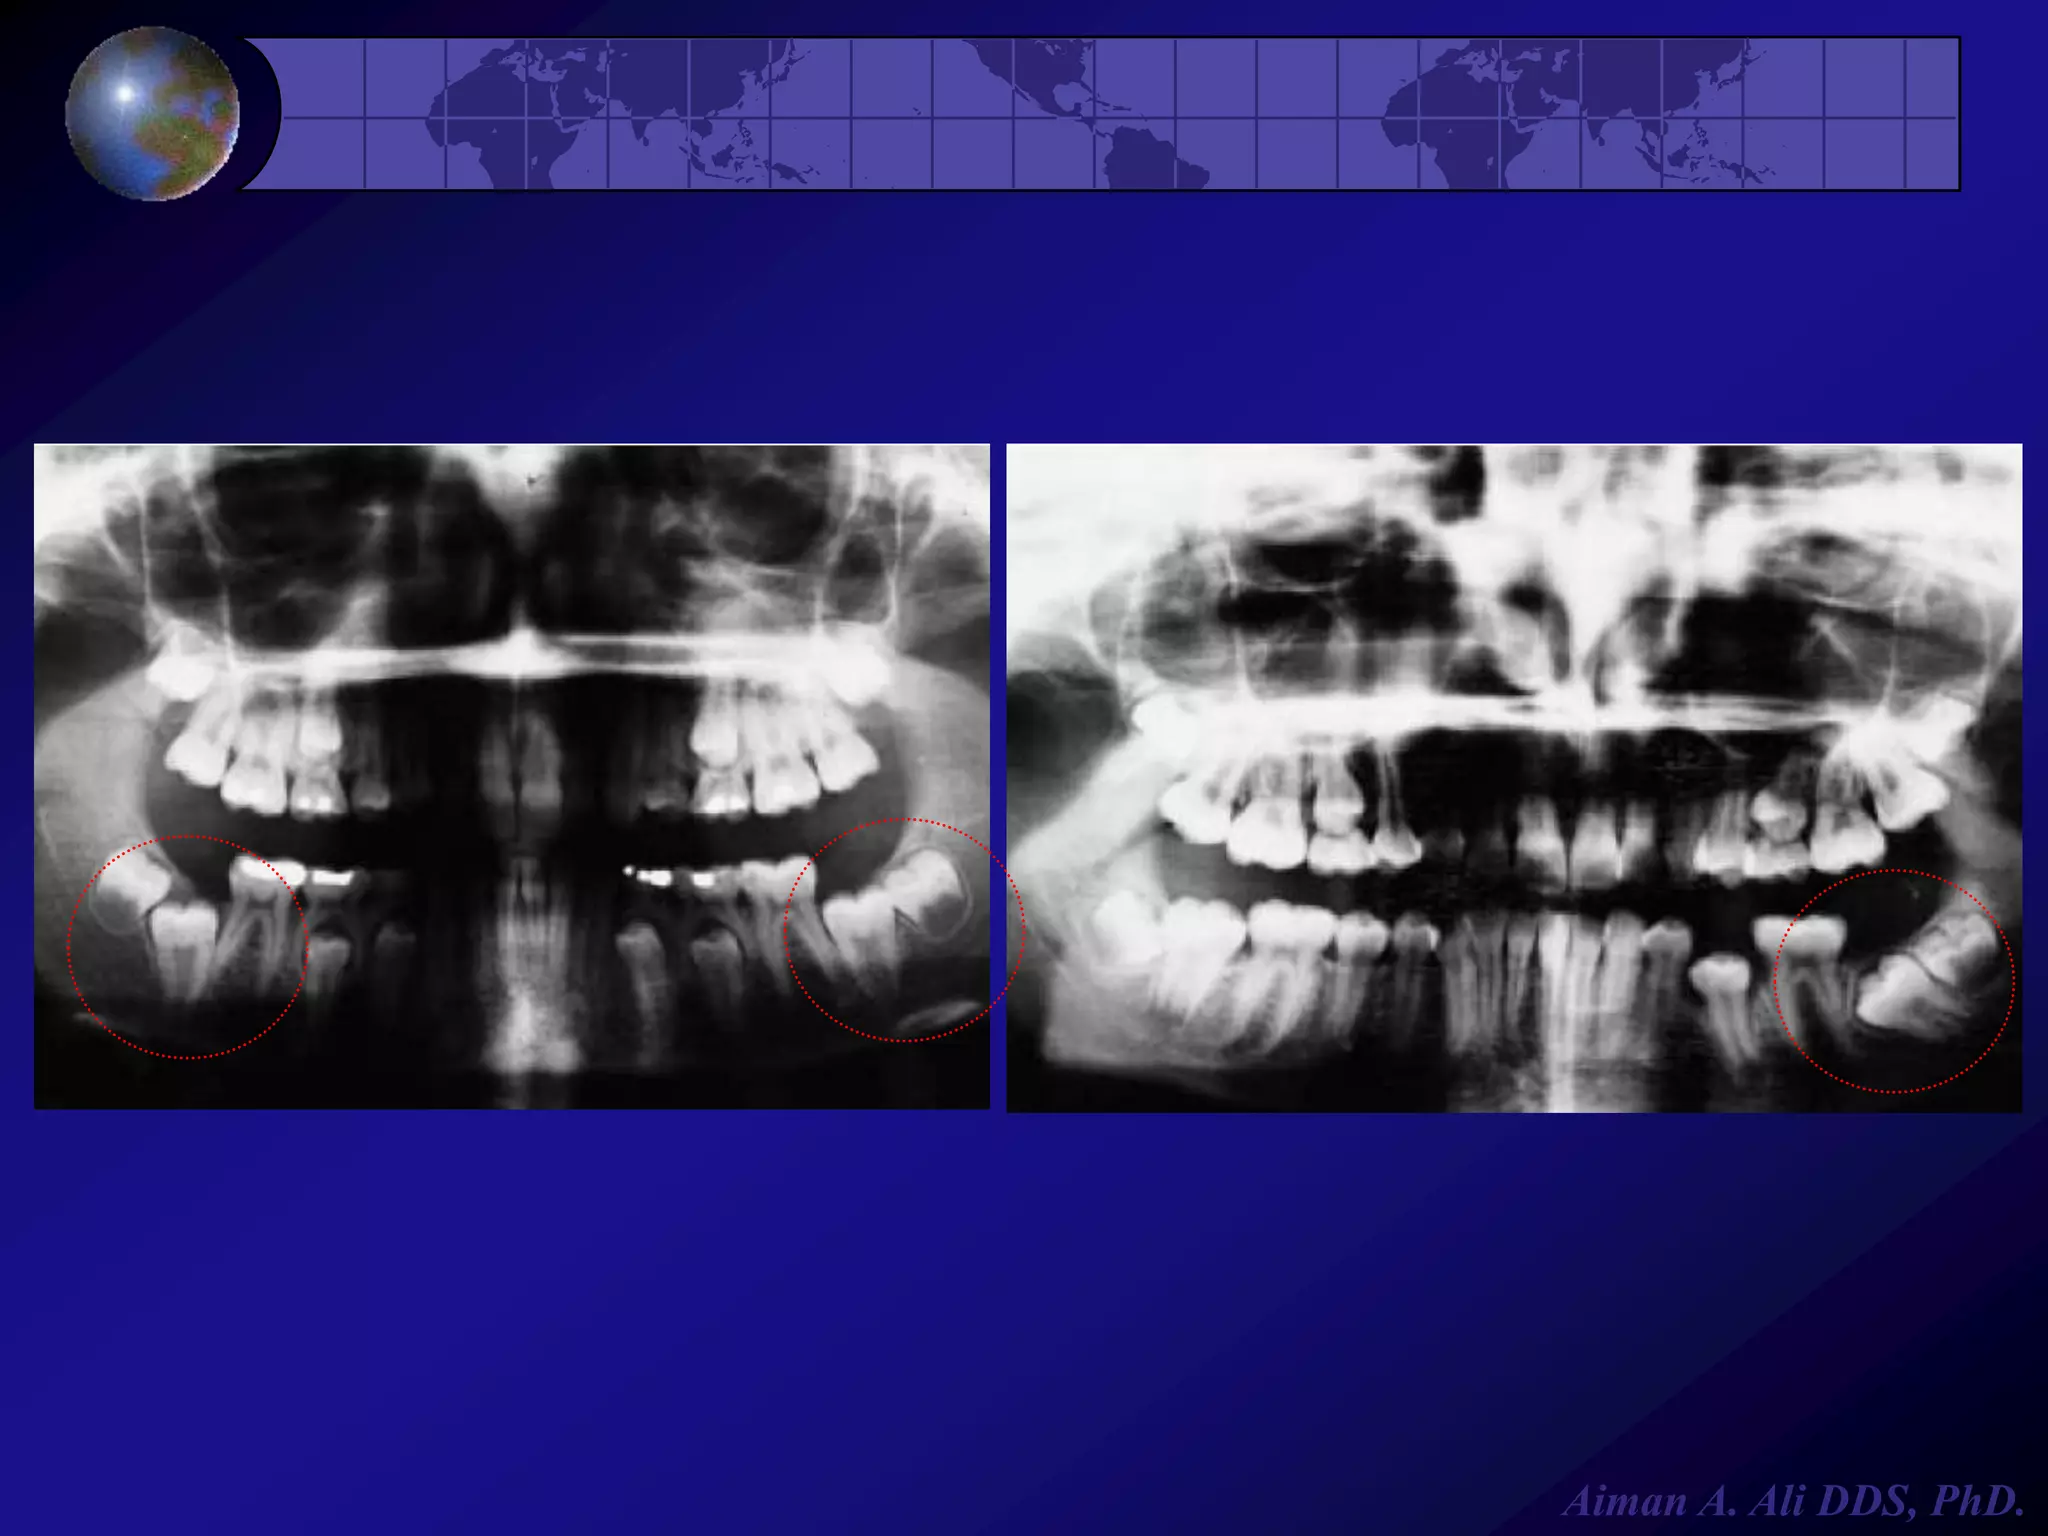

Alterations in Number

Impaction



It is most commonly seen in

mandibular third molars &

maxillary cuspids, it occurs

because of:



Crowding

Physical barrier

Abnormal eruption path

Ankylosis (fusion of tooth to

alveolar bone)

Aiman A. Ali DDS, PhD.